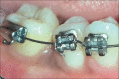

The interdisciplinary collaboration of periodontics and orthodontics has allowed teeth to be moved 2-3 times faster, reducing the time required for traditional orthodontic therapy considerably. Periodontally accelerated osteogenic orthodontics (PAOO), also known as Wilckodontics, is a combination of a selective decortication facilitated orthodontics and alveolar augmentation. With this technique, there is no dependence on the pre-existing alveolar volume. This case report describes the treatment of permanent mandibular molar protraction in a 14-year-old patient undergoing orthodontic therapy using PAOO with piezosurgery.